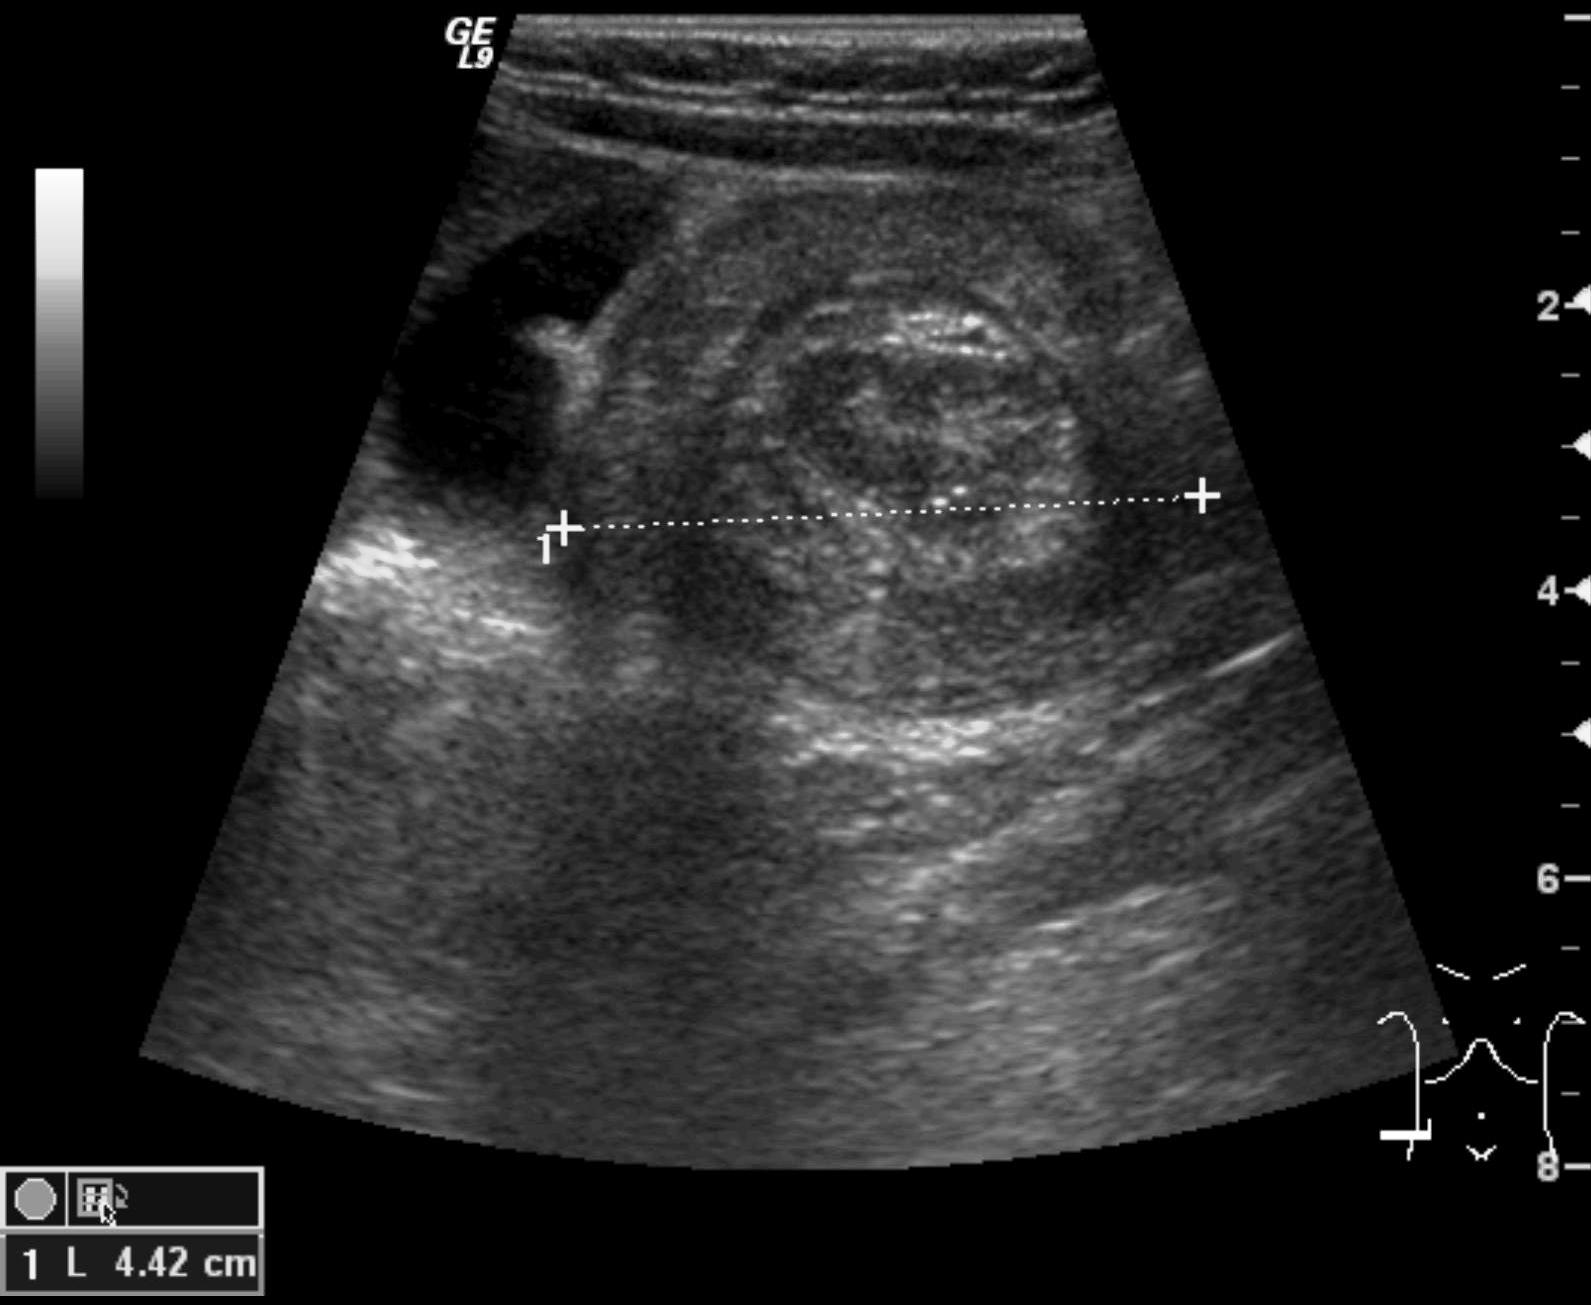

Invagination. A distal intestinal loop invaginating to a proximal intestinal loop can result in a mechanical intestinal obstruction, and cause ischemic damage. It most frequently occurs in infants (3-24 months) with recurring, colic-like complaints, distended intestines, a palpable mass and with frequent vomiting and bloody stool. Invagination requires immediate diagnosis and desinvagination. US exam reveals the invaginated intestines as a “target” sign in axial cross section and looks like a “pseudokidney” in longitudinal cross section. The therapy is hydrostatic or pneumatic desinvagination. Perforation and/or peritonitis are absolute contraindications to these procedures. Hydrostatic desinvagination can be performed under fluoroscopy or with US guidance and is considered successful if air or the contrast material appears in the terminal ileum and the invaginated loop disappears. If these efforts do not succeed, surgical desinvagination is needed.

17. “Target” sign. Invagination. .